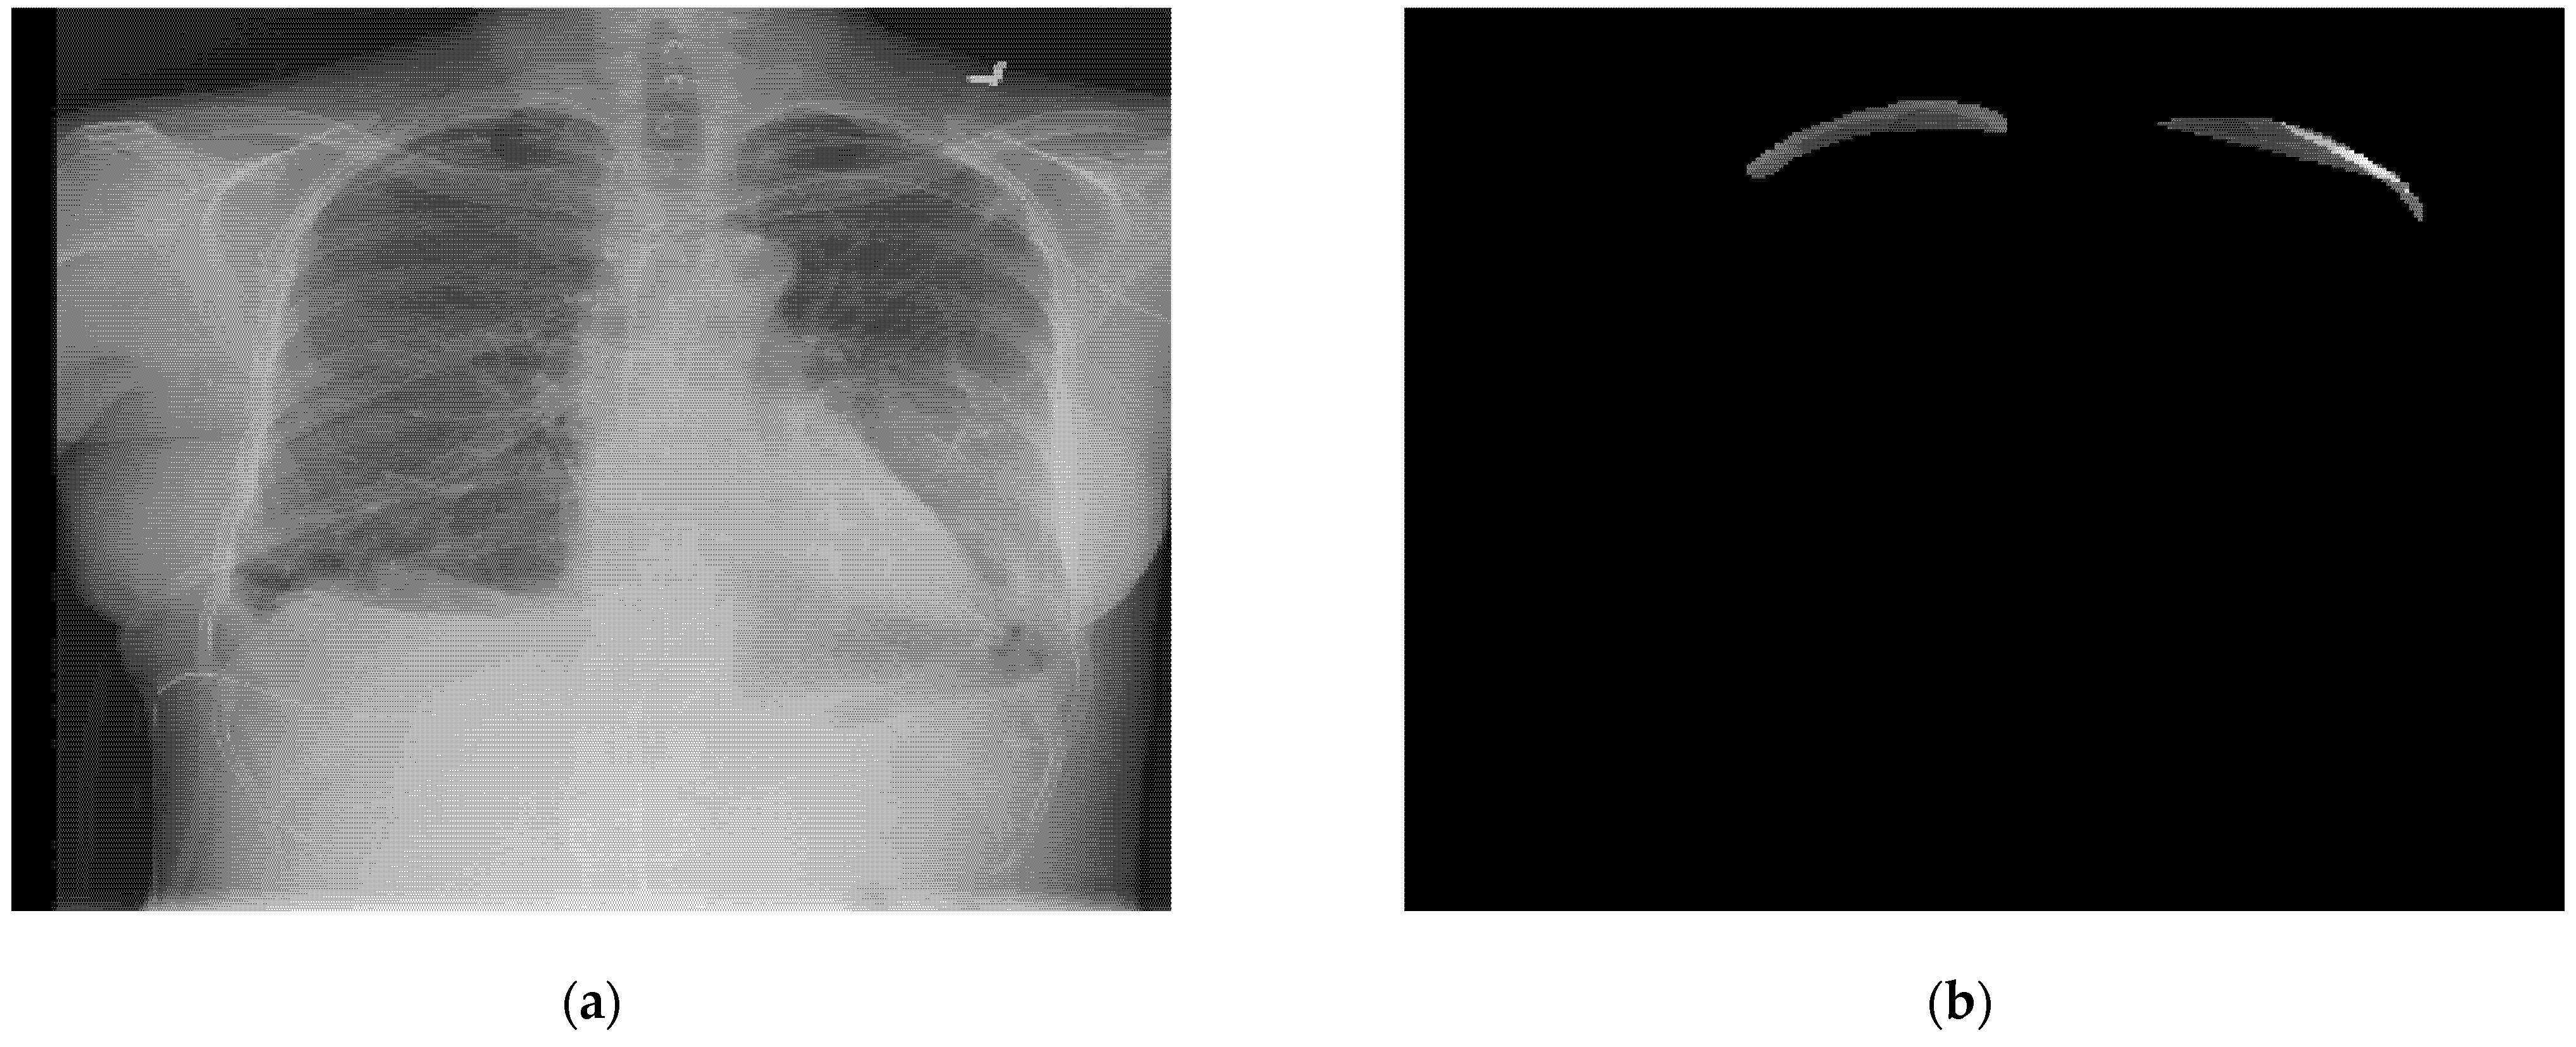

3. Dataset Analysis

5.1.3. RLE to Mask Conversion